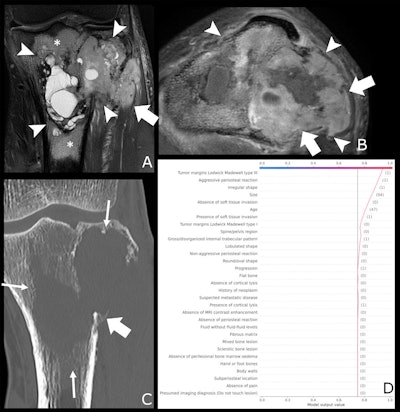

A 47-year-old male patient with knee pain for 10 months. (A) Coronal T2-weighted fat-saturated and (B) axial T1-weighted fat-saturated post-gadolinium MRI scans show a lytic lesion of the proximal tibia with an irregular shape (arrowheads), soft tissue invasion (fat arrow in A), and perilesional bone marrow edema (*). (C) Coronal CT image reconstructed with bone kernels of the same lesion show permeative margins (arrows) and a discontinuous periosteal reaction (fat arrow). (D) Shapley additive explanations decision function graph shows the impact of lesion characteristics on the ensemble classifier’s prediction. After a one-hot encoding for categorical features, present features are represented as "(1)" and absent features as "(0)," whereas continuous features are represented by the actual measurement. The estimated malignancy probability of this lesion was 0.94, which corresponds to Bone Tumor Imaging Reporting and Data System grade V. This lesion corresponded to an undifferentiated sarcoma at histologic examination and was graded as aggressive by the human reader.Radiology